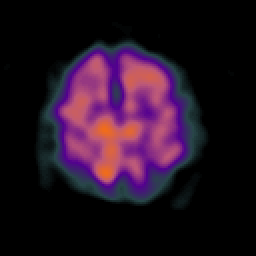

Alzheimer's disease: Perfusion SPECT -- Slice #38

[Home][Help][Clinical][Tour 1][Tour 2] Slice 38